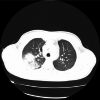

Figure 3. Cine balanced steady-state free precession (bSSFP) and late gadolinium enhancement (LGE) imaging

3A. Cine balanced steady-state free precession (bSSFP) imaging reveals a mass (white star) within the cavity of the right ventricle apex, with borders distinguishable from ventricular endothelium and trabeculation 3B: Late gadolinium enhancement (LGE) imaging shows no contrast uptake from the mass (white star), typical for an RV thrombus